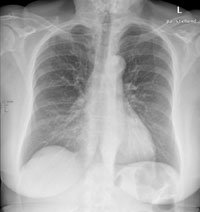

Eine 69-jährige Patientin klagt über einen seit mehr als 4 Wochen anhaltenden Husten mit wenig Auswurf. Die Frage nach Dyspnoe wird verneint. Fieber besteht keines.

Die körperliche Untersuchung ist unergiebig. Der behandelnde Arzt hat aufgrund der Raucheranamnese und des nicht enden wollenden Hustens ein Röntgenbild gemacht:

Thorax pa

Bild vergrössern

Welche Befunde fallen auf (mehrere richtige Antworten möglich)?

Wie beurteilen Sie nun das Röntgenbild?